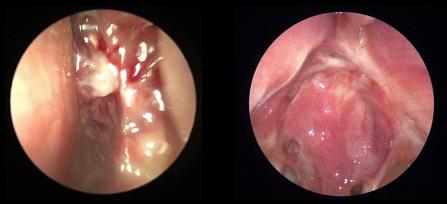

• Image

Postoperative appearance after removal of nasal polyps

Healthy, functional frontal sinuses after surgery to remove nasal polyps (extended Draf III frontal sinusotomy)

Functional endoscopic sinus surgery: The goal of this minimally invasive surgery is to restore the natural drainage to the sinuses. It also allows the application of topical medications to treat the sinuses.

Nasal cavity polyps obstructing the sinuses

Nasal cavity polyps obstructing the sinuses before surgery

Polypectomy: This in-office treatment is used to remove nasal polyps.